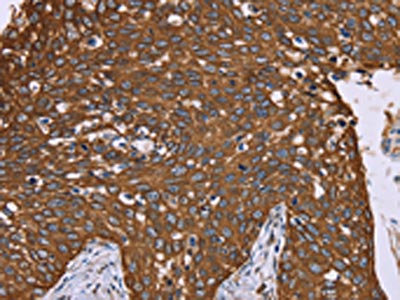

The image on the left is immunohistochemistry of paraffin-embedded Human cervical cancer tissue using CSB-PA906437(PPIB Antibody) at dilution 1/40, on the right is treated with fusion protein. (Original magnification: ×200)

The image on the left is immunohistochemistry of paraffin-embedded Human liver cancer tissue using CSB-PA906437(PPIB Antibody) at dilution 1/40, on the right is treated with fusion protein. (Original magnification: ×200)